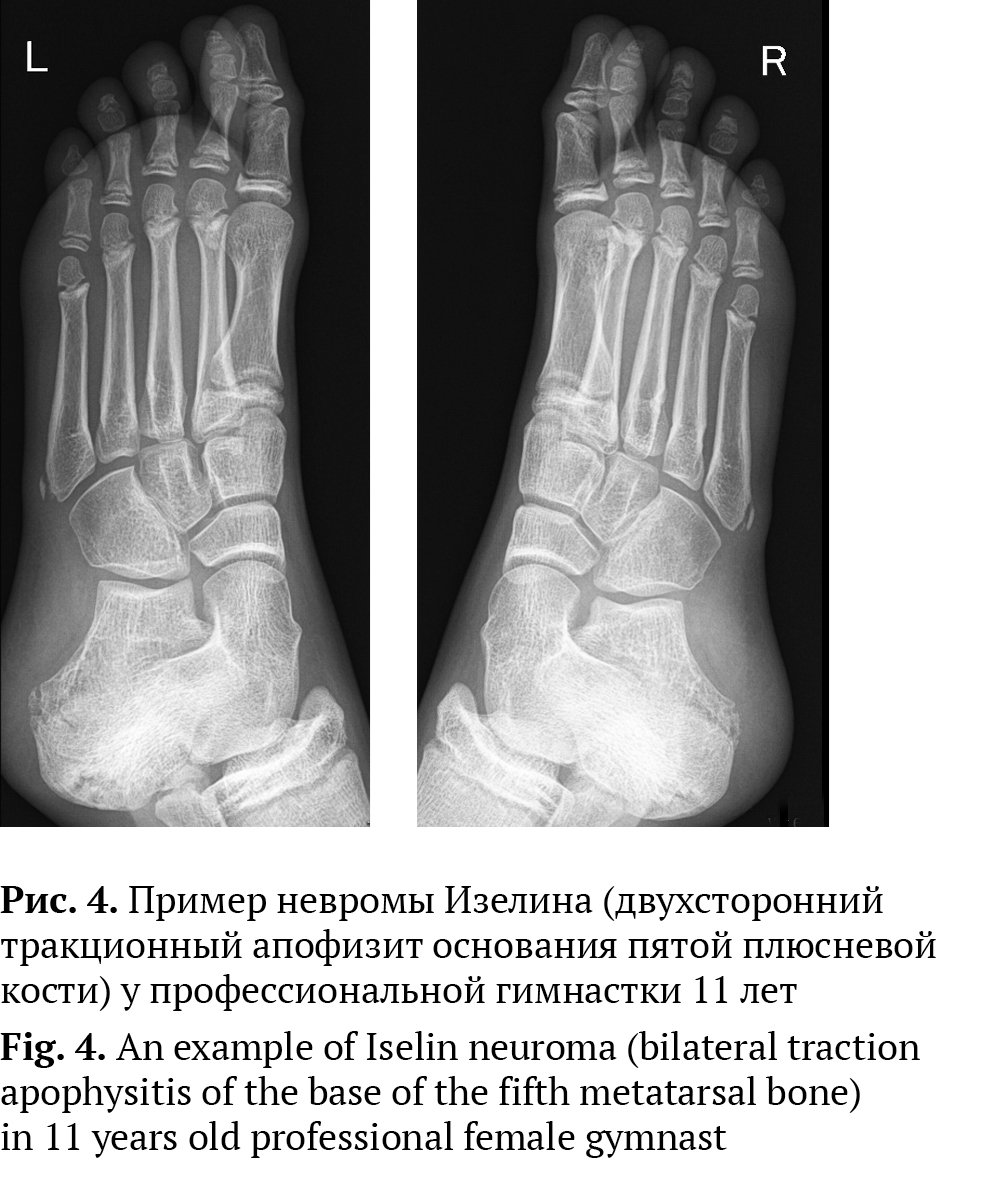

Неврома четвертого межплюсневого промежутка получила свое название в честь Изелина (Iselin), ортопеда, описавшего в 1912 г. тракционный апофизит основания пятой плюсневой кости у подростков в момент появления вторичного очага окостенения основания пятой плюсневой кости (рис. 4). Для данного заболевания характерна боль в области внешнего края средней части стопы, которая усиливается при повышенной физической нагрузке (бег, прыжки, танцы) [цит. по 23]. По мнению Э.Э. Ларсон (E.E. Larson) с соавторами, в дальнейшем имя хирурга стало ассоциироваться с невропатической болью в четвертом межпальцевом промежутке, что и привело к появлению термина «неврома Изелина» [6].

Рис. 4. Пример невромы Изелина (двухсторонний тракционный апофизит основания пятой плюсневой кости) у профессиональной гимнастки 11 лет

Fig. 4. An example of Iselin neuroma (bilateral traction apophysitis of the base of the fifth metatarsal bone) in 11 years old professional female gymnast

Заболевание, именуемое «неврома Мортона», должно носить название «фиброз третьего подошвенного пальцевого нерва». А именные термины, в некоторых случаях не имеющие отношения к заболеванию, желательно заменить на номер соответствующего общего нерва. Например, в случае невромы Изелина — фиброз четвертого подошвенного пальцевого нерва и т.д.